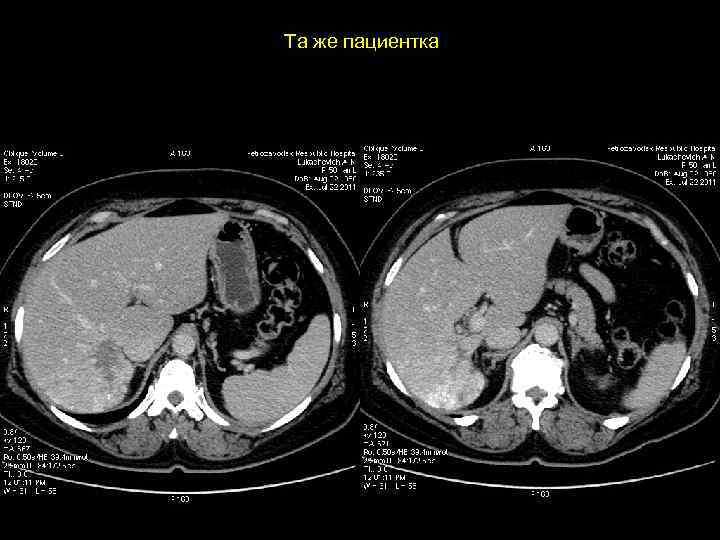

Клиническое наблюдение. Пациентка К, 1966 г. р.

Та же пациентка